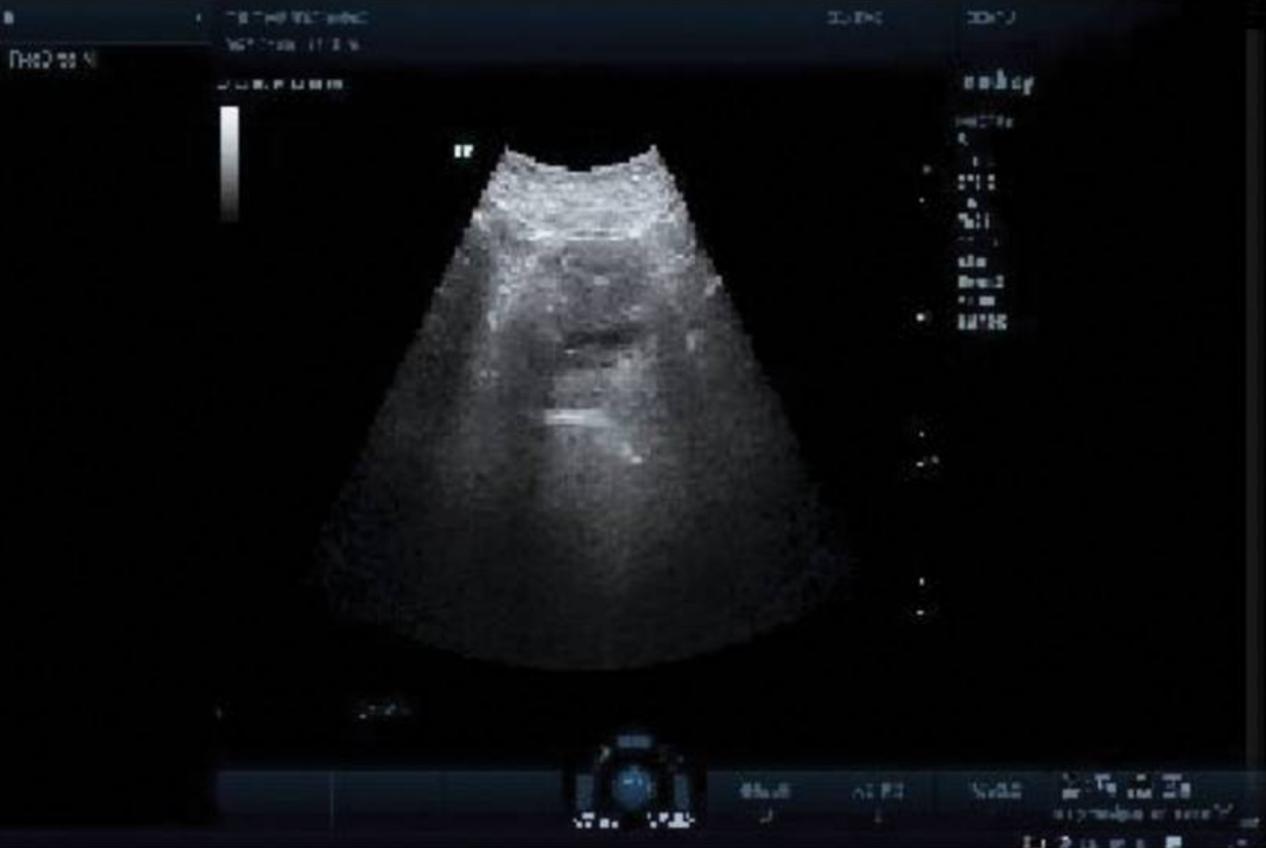

图4 在随后的治疗结束时,他已经完全康复,排尿后不再出现残余尿液

尿动力学检查表明(i)膀胱的尿路感觉和膀胱顺应性正常,(ii)膀胱测量容积正常,(iii)从灌注开始到灌注结束,未观察到逼尿肌的不自主收缩和冲动性失禁,(iv)膀胱流出道可能存在梗阻,(v)膀胱排空正常(图5)。